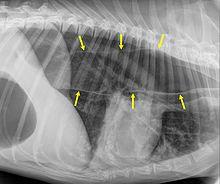

An x-ray of the thorax of a dog with megaoesophagus. The edges of the esophagus are shown by the yellow arrows. (In this image, the head end of the dog is to the right, and the tail end is to the left